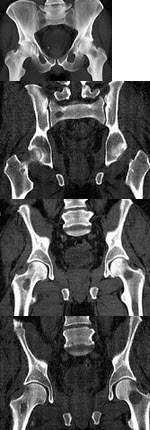

6、单项选择题

男,8岁,右髋疼痛,活动受限,结合图像,最可能的诊断是()

A.股骨头骨骺缺血坏死

B.髋关节结核

C.剥脱性骨软骨炎

D.退行性骨关节病

E.骨纤维异常增殖症

B.口服胆囊造影

133、单项选择题

男,46岁,双髋部疼痛,实验室检查血钙升高,尿本周蛋白(+),结合图像,最可能的诊断是()

A.骨髓瘤

B.骨质疏松症

C.骨转移瘤

D.骨囊肿

E.动脉瘤样骨囊肿